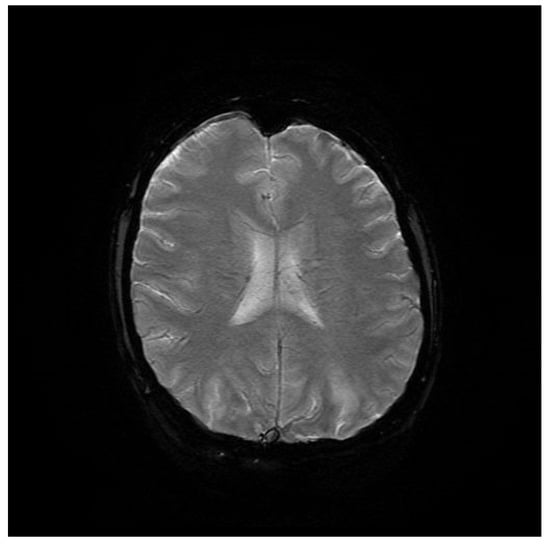

Computed tomography (CT) angiography of the head and CT with contrast were performed and excluded aneurysm, arteriovenous malformation (AVM), dural sinus thrombosis, and tumor. Due to the lack of deviations in the previous tests, an MRI of the head with contrast was performed, in which small areas and hyperintense bands in the T2-weighted image (T2-WI) and Fluid Attenuated Inversion Recovery (FLAIR) were visualized on both sides in the parieto-occipital areas without either diffusion restrictions or contrast enhancement, a typical manifestation of PRES [4], as shown in Figure 1, Figure 2, Figure 3 and Figure 4.

Figure 2. FLAIR MRI sequence of the brain.